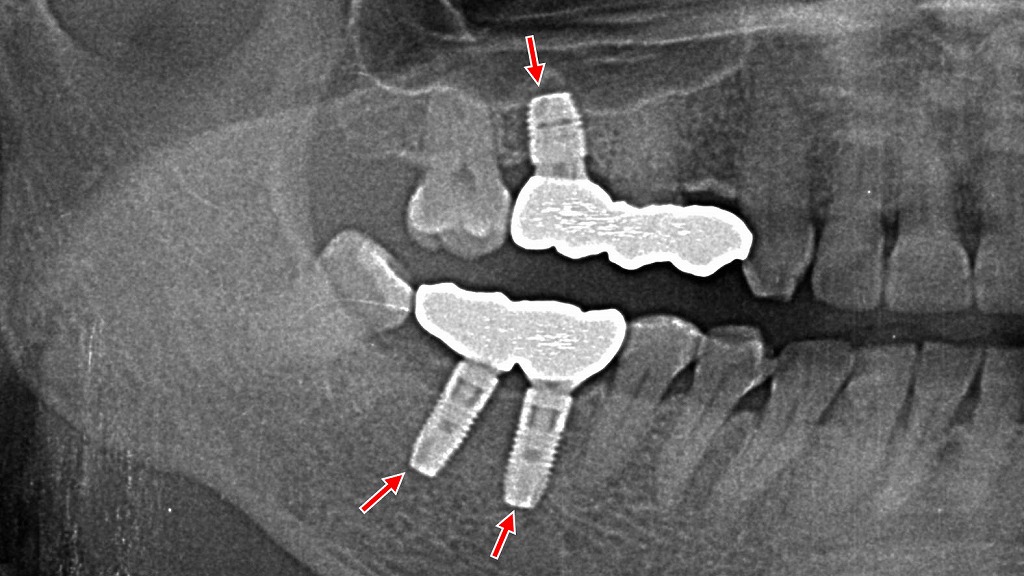

⚠️ 維持歯への負担と寿命への影響

部分入れ歯は、残っている歯(維持歯)にクラスプをかけて支える構造です。これにより、横揺れなどの負担が集中しやすく、歯槽骨が吸収されて歯がグラグラになる可能性も。維持歯の寿命が短くなるリスクがあるため、定期的なチェックが重要です。